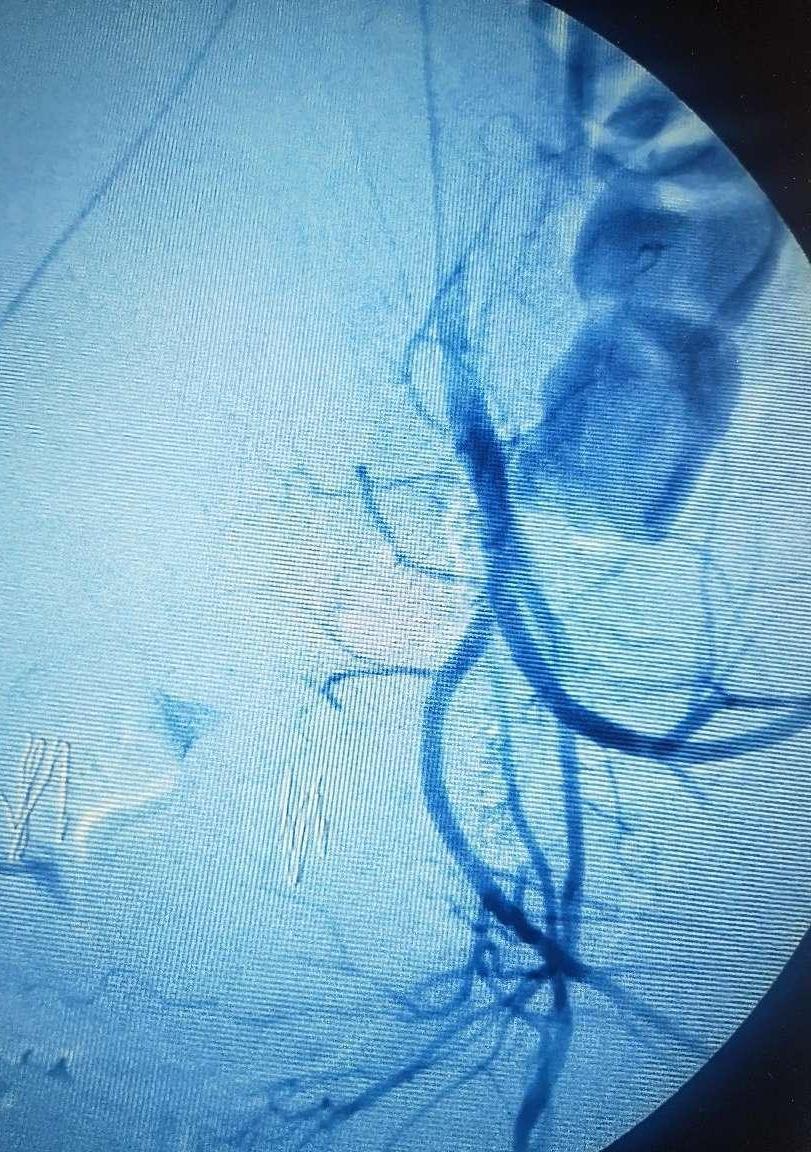

徐州市妇幼保健院放射介入团队杜长江主治医师、李兆宸医师第一时间赶到查看患者,充分了解患者病情后,排除介入手术禁忌,与患者及其家属充分沟通后,立即联合手术室、麻醉科,积极完善各项手术前准备。局部麻醉下,医生通过右股动脉穿刺,成功置管于双侧髂内动脉及子宫动脉进行造影。造影结果显示,双侧子宫动脉明显增粗、迂曲,将子宫动脉导管分别置于双侧子宫动脉开口处,缓慢注入适量明胶海绵颗粒,阻塞出血责任血管,有效控制了出血。手术在患者全程清醒状态顺利完成,术后患者恢复较好,无明显不适,未发生严重手术并发症。

对于难治性子宫出血的患者,保守治疗效果不佳时,手术治疗往往是有效办法,手术方式包括:子宫压迫缝合术、盆腔血管结扎术、介入治疗以及子宫切除等。常规开腹止血手术创面大,对患者身体及心理均有较大打击。介入手术在不用开刀暴露病灶的情况下,仅需通过血管穿刺,在影像设备的导引下,经血管插入导管对出血的部位进行造影,明确出血部位,并注入栓塞物质封堵出血部位的血管进行止血,与常规手术比较,介入具有微创、恢复快、疗效确切、可重复、精准及并发症少的优势,可以在短时间内控制出血,且手术安全有效,能够保留患者的子宫和生育功能,减少身体和心理上的创伤。因此子宫动脉栓塞广泛应用于难治性产后出血、瘢痕妊娠术前预处理等。